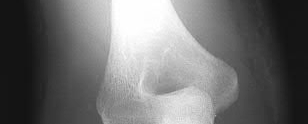

Figure A is an AP radiograph of a posterior knee dislocation. Figure B is a lateral showing the same injury.